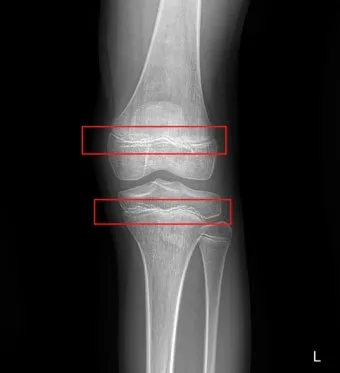

성장판은 하나의 문이 갑자기 '딱' 닫히는 것이 아닙니다. 손가락, 발가락, 손목, 발목, 골반, 척추 순으로 뼈 끝 쪽의 연골이 굳어져 가는 과정은 꽤 오랜 시간이 걸려요. 성장판의 닫히는 시기는 개인차가 매우 크답니다.

일반적으로 여성은 14-15세, 남성은 16-17세에 성장판이 닫히기 시작하지만, 완전히 닫히는 것은 만 19-20세경이에요. 하지만 여기서 중요한 건, 성장판 검사에서 '닫혔다'고 나와도 검사 오차가 있을 수 있고, 미세하게 남아있는 성장판으로 인한 성장 가능성이 남아있다는 점입니다.